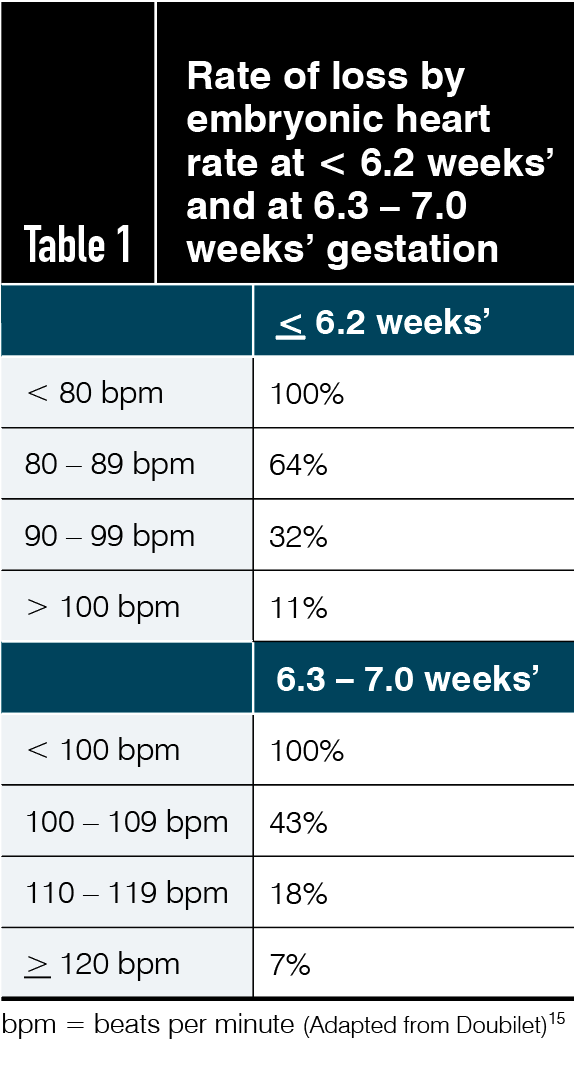

How to detect early miscarriage. How doctors diagnose miscarriage quantitative hcg blood test. A lab can examine the tissue to check for signs of a miscarriage. What is an early miscarriage and how common is it?

Passing tissue or blood clots from the vagina. Doctors describe an early miscarriage as one that happens in the first 12 weeks of pregnancy (rcog 2016a). Since most early miscarriages are caused by problems specific to that fertilized egg, and miscarriage overall is relatively common, most experts do not recommend special.

In most cases, an ultrasound scan can determine if you're having a miscarriage. The signs of early miscarriage will depend on the gestation of your pregnancy. It may feel crampy or persistent,.

Call your doctor if you think you’re having a miscarriage. Detecting miscarriage is not always straightforward “a lot of people come in with bleeding and are justifiably nervous,” says dr. If these symptoms happen early enough—or if you haven't received a positive pregnancy test.

After 12 weeks, and before 24 weeks of pregnancy, it’s called. Key points early miscarriages are very common and one in five women have a miscarriage for no apparent reason. Keep in mind that most pregnant people who have vaginal spotting or bleeding in the first trimester go on to have.